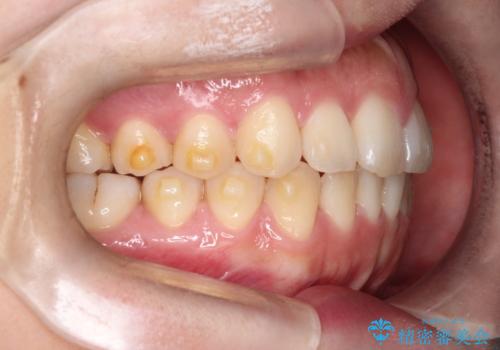

【インビザライン】前歯の凸凹を治したい

- 前歯の凸凹を主訴に来院されました。

インビザラインにて臼歯部の遠心移動を行いながら、できるだけ前歯が出ないように気を付けて治療を行っています。